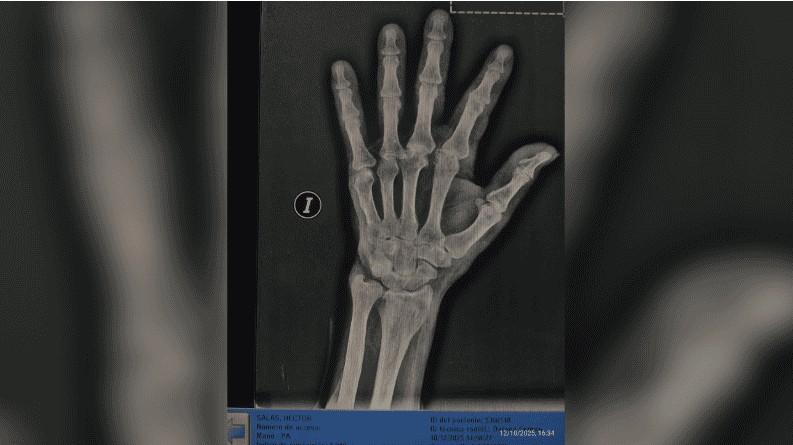

La nieta de la víctima, Karen Salas, realizó una denuncia pública a través de las redes sociales y apuntó directamente contra la responsable del lugar. “Él se negó a tomar una medicación y ella (la dueña del geriátrico) fue y le pegó. Según ella, dijo que le pegó porque le agarró un brote psicótico”, expresó. En la publicación compartió imágenes del estado de su abuelo, registros de las cámaras internas y las radiografías realizadas tras la agresión.

Luego del episodio, Héctor fue retirado del geriátrico y trasladado a otro establecimiento. Según indicó la familia, tras una revisión médica solicitada por sus nietas se confirmaron fracturas en el dedo pulgar derecho y heridas en el rostro.